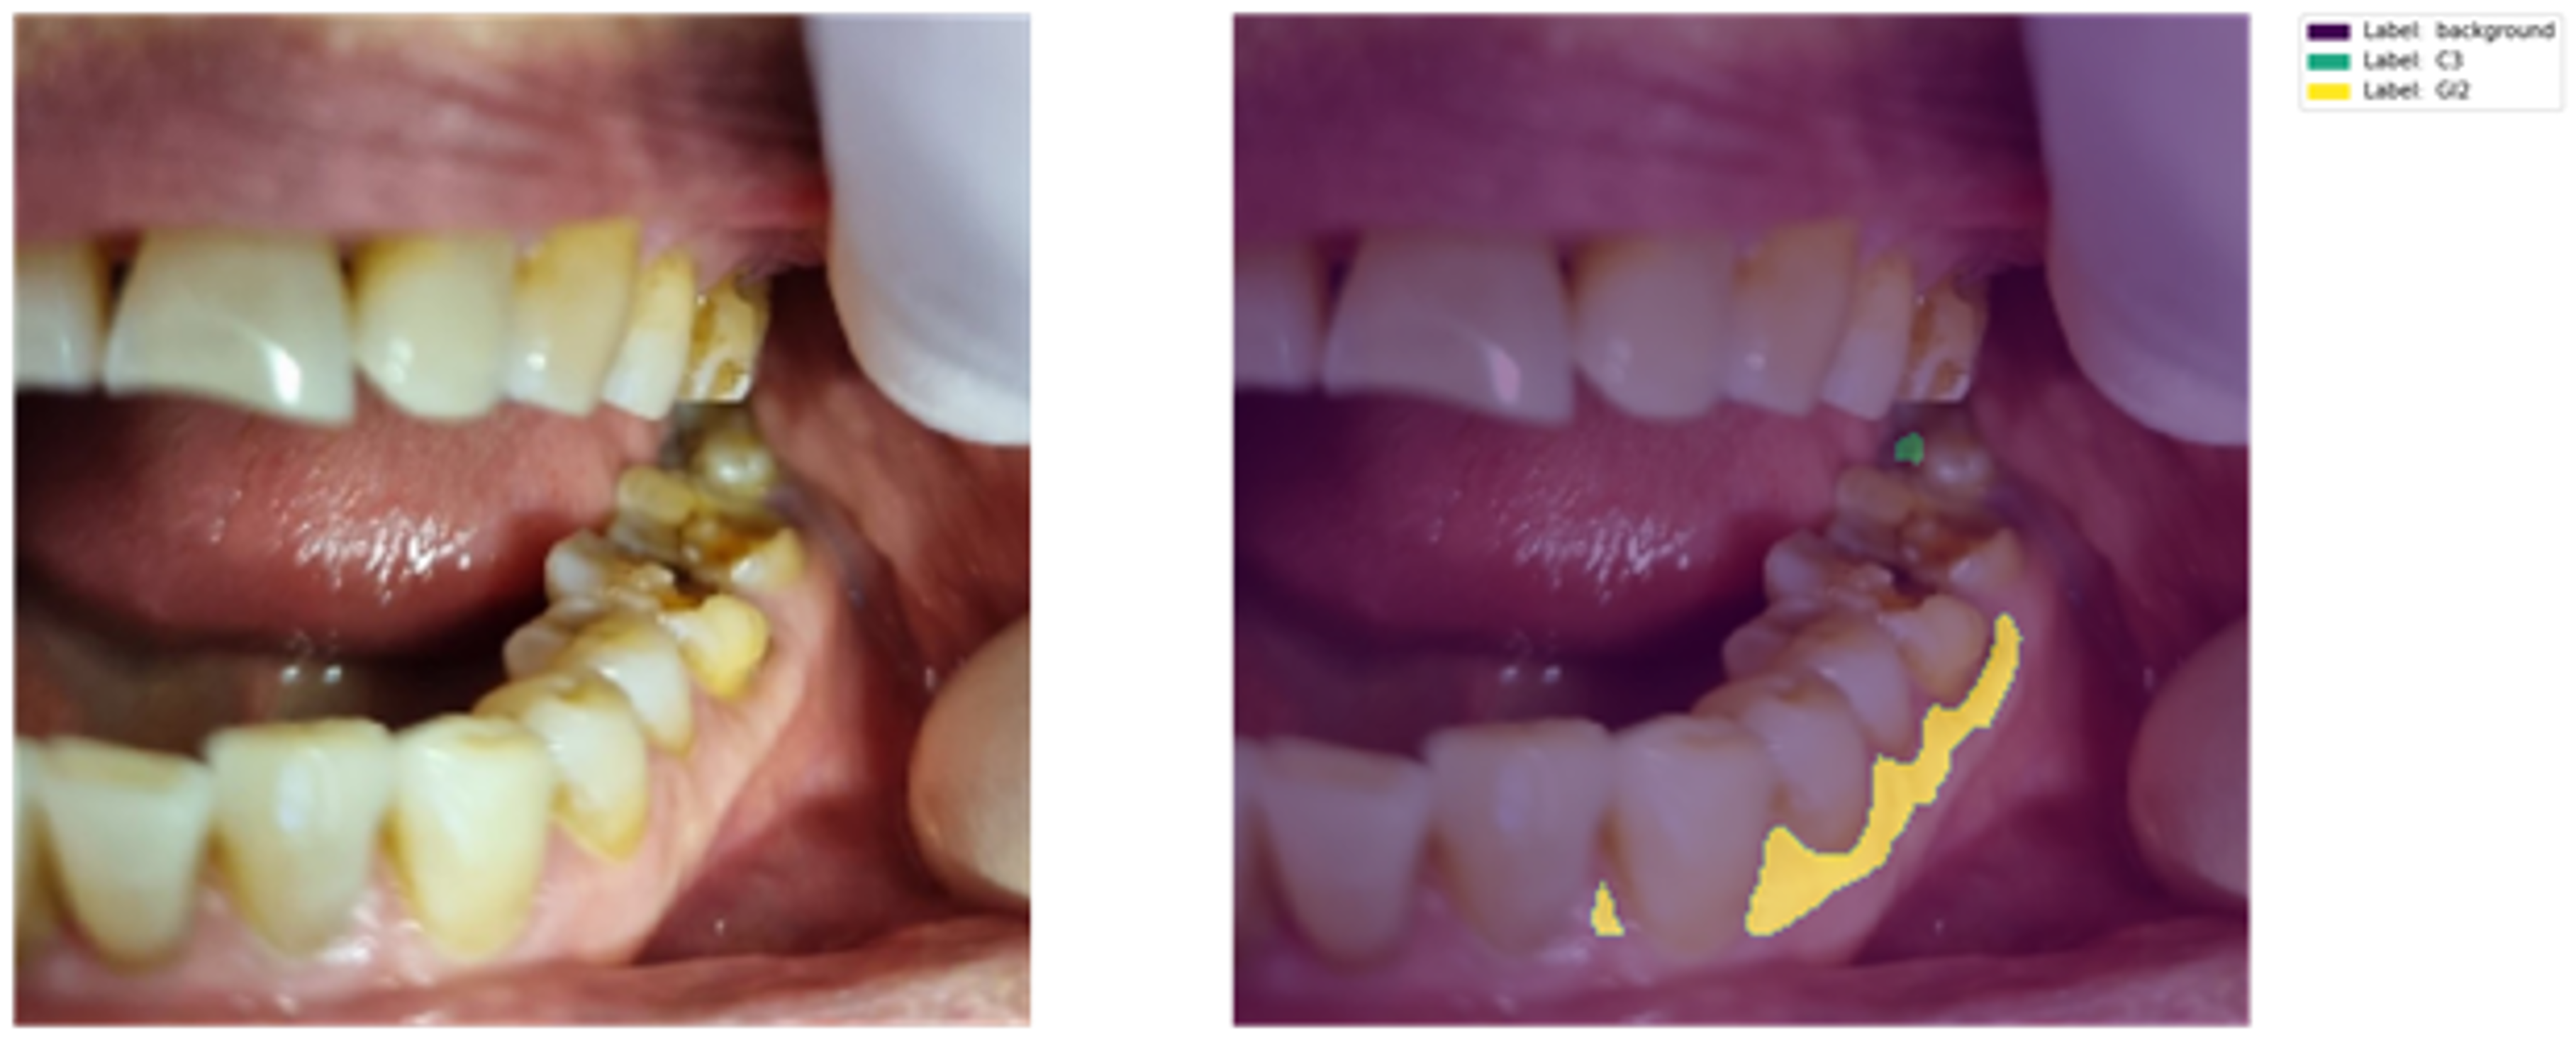

● 첨단 치의학 도시인 부산시의 고령층 구강질환 개선을 위하여 치과에서 생성되는 의료 데이터가 아닌 일상 데이터를 습득 ● 구강 이미지 및 문진 자료를 수집하고 이미지 내 치아 번호, 치아우식, 치주질환, 치석, 보철물 등 구강 내 다양한 상태를 레이블링하여 고품질 데이터 확보

● 다양한 구강질환을 검출할 수 있는 인공지능을 학습시키기 위한 구강 Data-Set 구축 ● 일반 카메라로 촬영된 구강 이미지 데이터를 활용한 다양한 기술개발 촉진 ● 이미지, 문진 데이터를 기반으로 한 한국형 구강 통계 산출

c. 치주질환(충치, 치주염, 치은염) 탐지 모델

목표 : 치주질환 탐지

- 모델 : Unet Plus Plus (Unet++) (설명 생략)

● 질환

| 3-1-1 | label | string | y | C1 | |||||||

| C2 | |||||||||||

| C3 | |||||||||||

| GI1 | |||||||||||

| GI2 | |||||||||||

| GI3 | |||||||||||

| PDI1 | |||||||||||

| PDI2 | |||||||||||

| PDI3 | |||||||||||